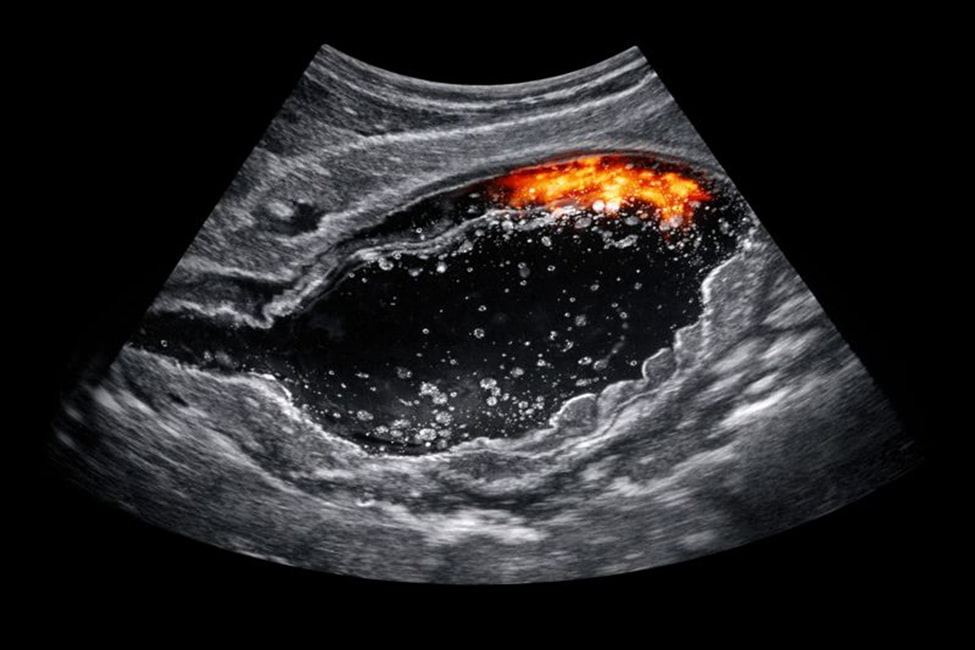

УЗИ желудка с водно-сифонной пробой относится к современным методам ультразвуковой визуализации, которые применяются для оценки не только анатомии, но и функциональных особенностей органов верхнего отдела пищеварительной системы. Исследование широко используется в клинической практике благодаря сочетанию информативности и безопасности.

УЗИ желудка с водно-сифонной пробой производится в рамках диагностического подхода, при котором ультразвуковое сканирование выполняется в несколько этапов с использованием водной нагрузки. Это позволяет лучше визуализировать внутренние контуры органа и оценивать его реакцию на наполнение.

Во время исследования врач получает возможность рассмотреть пищевод, начальные отделы двенадцатиперстной кишки и окружающую ее область в реальном времени. Это расширяет диагностические возможности и позволяет выявлять функциональные особенности, которые не видны при стандартном УЗИ.

Ультразвуковое исследование желудка с водно-сифонной пробой дает расширенную информацию о форме органа, толщине стенок и характере сокращений. Специалист может оценивать реакцию желудка на поступление жидкости и особенности ее распределения.

Кроме того, метод помогает выявлять функциональные отклонения, задержку эвакуации и изменения, которые отражают текущее состояние слизистой оболочки. Эти данные важны для постановки диагноза и выбора дальнейшей тактики наблюдения.